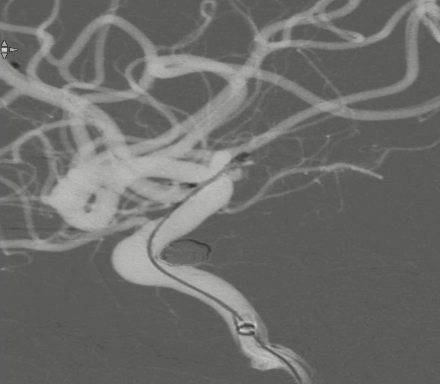

术前外院 DSA 2025-02

箭头所指右侧A1微小动脉瘤

工作位正位造影(图片)

工作位侧位造影(图片)

工作位正位造影(视频)

工作位侧位造影(视频)